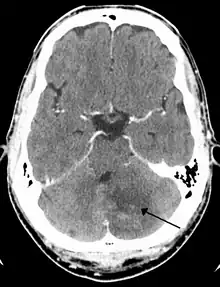

Cerebellar stroke syndrome is a condition in which the circulation to the cerebellum is impaired due to a lesion of the superior cerebellar artery, anterior inferior cerebellar artery or the posterior inferior cerebellar artery.[1]

Cerebellar strokes account for only 2-3% of the 600,000 strokes that occur each year in the United States.[3] They are far less common than strokes which occur in the cerebral hemispheres. In recent years mortality rates have decreased due to advancements in health care which include earlier diagnosis through MRI and CT scanning.[4] Advancements have also been made which allow earlier management for common complications of cerebellar stroke such as brainstem compression and hydrocephalus.[4]